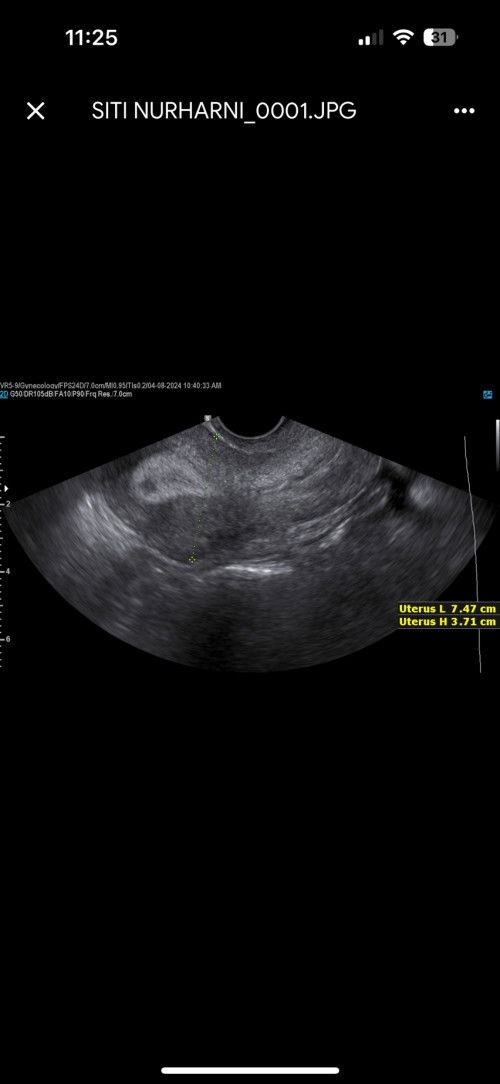

hi momy nak tanya ada tak pengalaman scan rahim nampak tebal dan hari ke 18 ada telur matang yg nampak seakaan bakal pecah sbb saya last period 18/7 . ada ke momy yg pandai tengok scan ? tapi ada dr kata rahim saya nampak garisan tak sekata mana tau dalam ni ada yg boleh share , tertanya jugak … sbb saya jugak ada ambik vitamnin D3 dan folid acid ... #SeriusTanya #ttcjourney